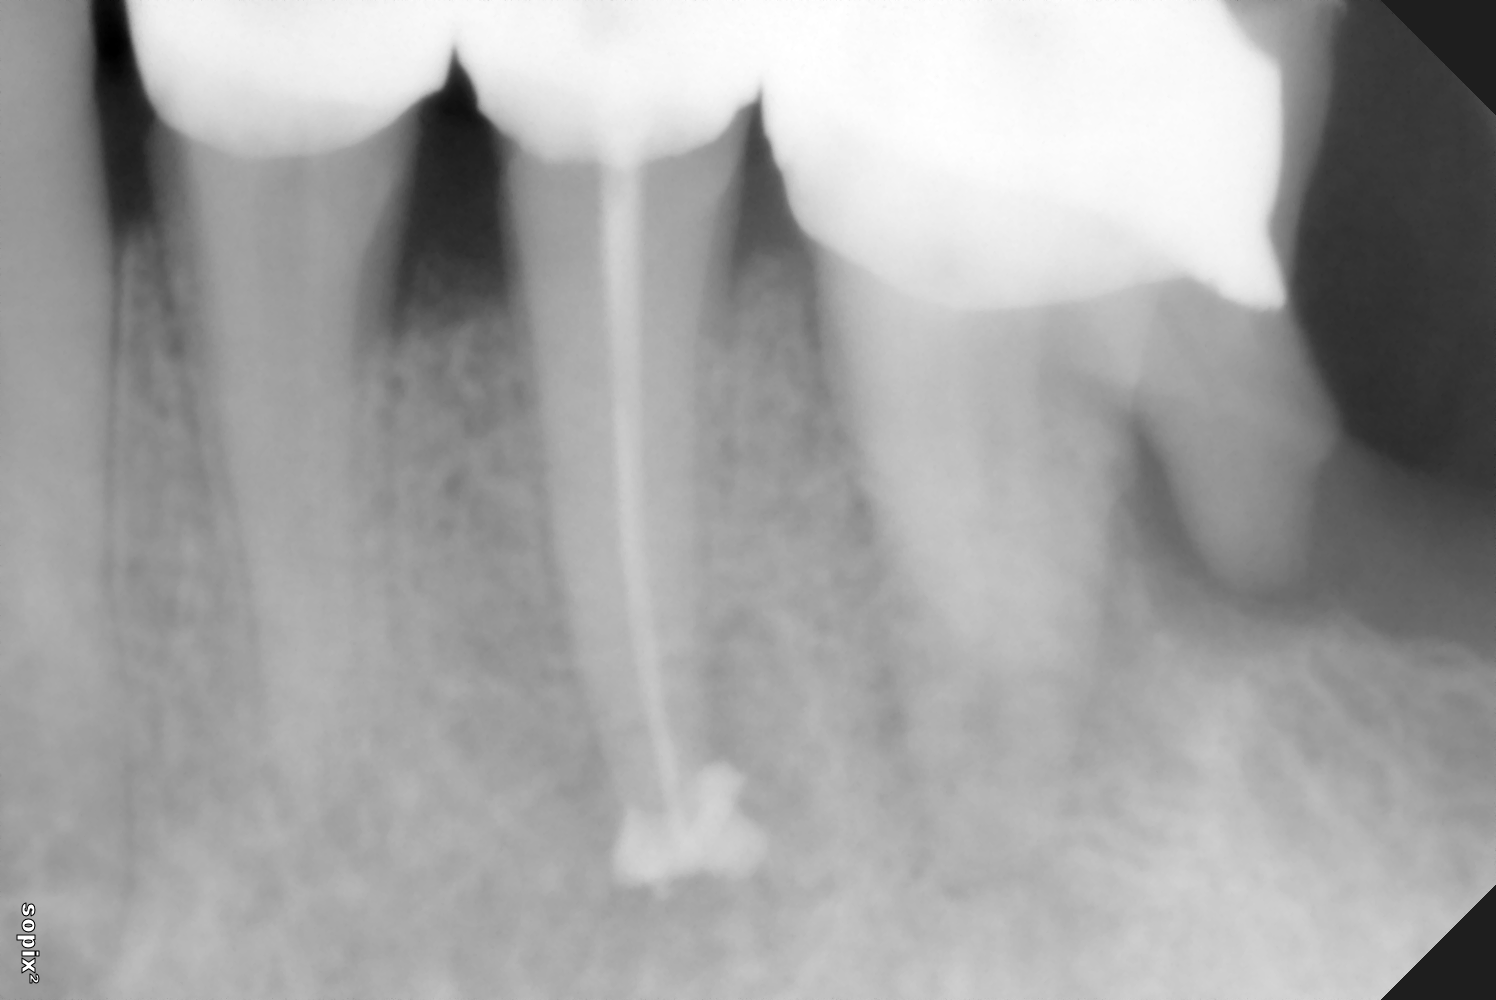

Η ενδοδοντική θεραπεία, η γνωστή απονεύρωση, αποτελεί πάντοτε μια πρόκληση που στόχο έχει να διατηρήσει το δόντι μέσα στο στόμα μας. |